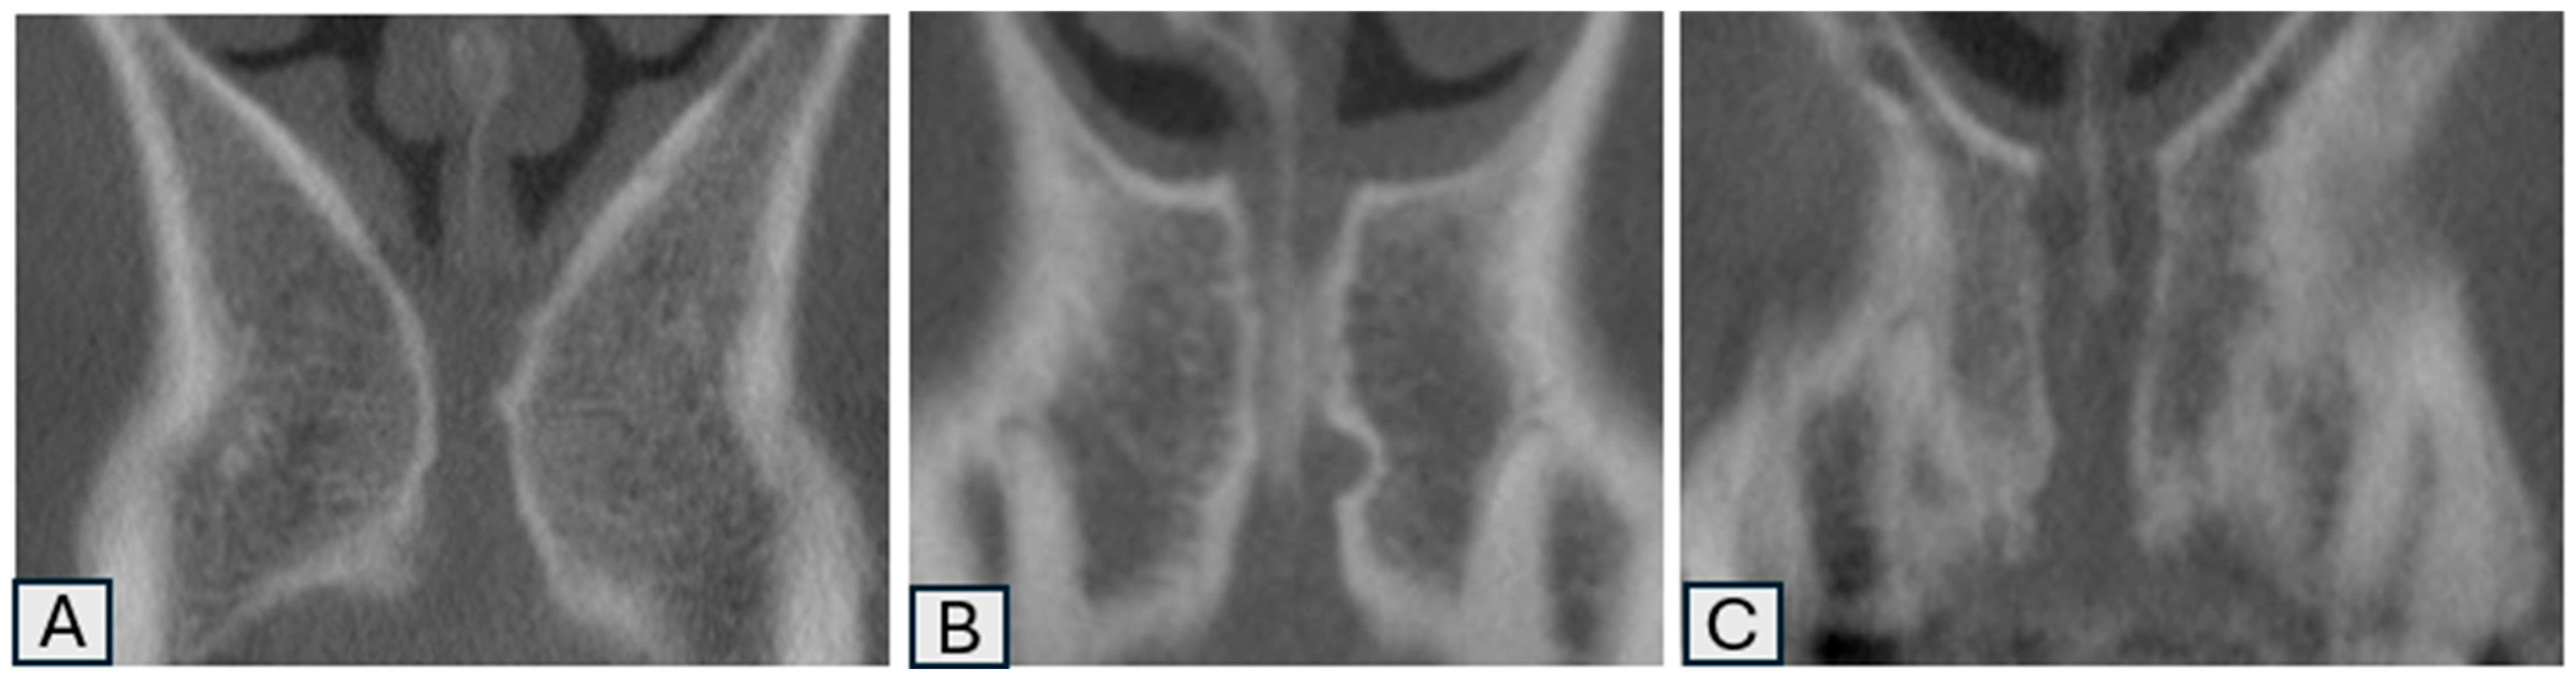

| Morphology of the nasopalatine canal (Sagittal) | Cylindrical | 83 | 44.9% |

| Cone | 47 | 25.4% | |

| Funnel | 41 | 22.1% | |

| Banana-shaped | 3 | 1.6% | |

| Hourglass-shaped | 8 | 4.3% | |

| Tree branch | 3 | 1.6% | |

| Morphology of the nasopalatine canal (Coronal) | Single | 97 | 52.4% |

| 2 parallel | 23 | 12.4% | |

| Y-shaped | 65 | 35.1% | |